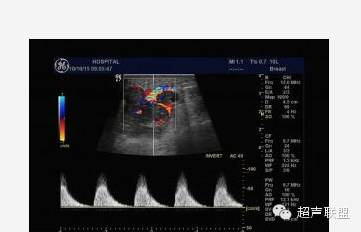

声像图表现:于右乳腺相当于六点钟,距约1.5cm处见一大小约1.0x0.6cm低回声肿物,边界尚清,形态不规,周边可检出动脉频谱样血流信号,RI为0.67,余腺体回声粗糙,未见占位性病变。右腋下另见数个淋巴结,较大的为1.4x0.8cm,边界清,周边呈低回声,中心部呈高回声。

超声印诊:1.右乳腺低回声肿物,性质待定

2.右腋下淋巴结肿大

病理结果:浆细胞性乳腺炎

签别诊断:主要是和乳腺Ca的签别,癌肿内还可以有“沙粒样”的微钙化灶,浆细胞性乳腺炎的病灶内血管多为低阻力型,RI一般小于0.70;乳腺癌的病灶内血管一般为高阻力型,RI多数大于0.70。(其机理是由于肿瘤血管在解剖结构上缺乏肌层,且没有一般血管从近端到远端逐渐变细的特点,导致局部受压,使血管阻力升高;而浆细胞性乳腺炎则无上述特点)。当图象上两者有交叉不好区分时,结合病史是最关键的,浆细胞性乳腺炎既往可有红、肿、热、痛的病史,急性期和亚急性期的结节有触痛,常有导管扩张,慢性期的结节可存在数年之久,抗生素治疗无效时,应想到本病的可能性;乳腺癌患者常无症状,仅触及包块,病史短,不伴导管扩张。